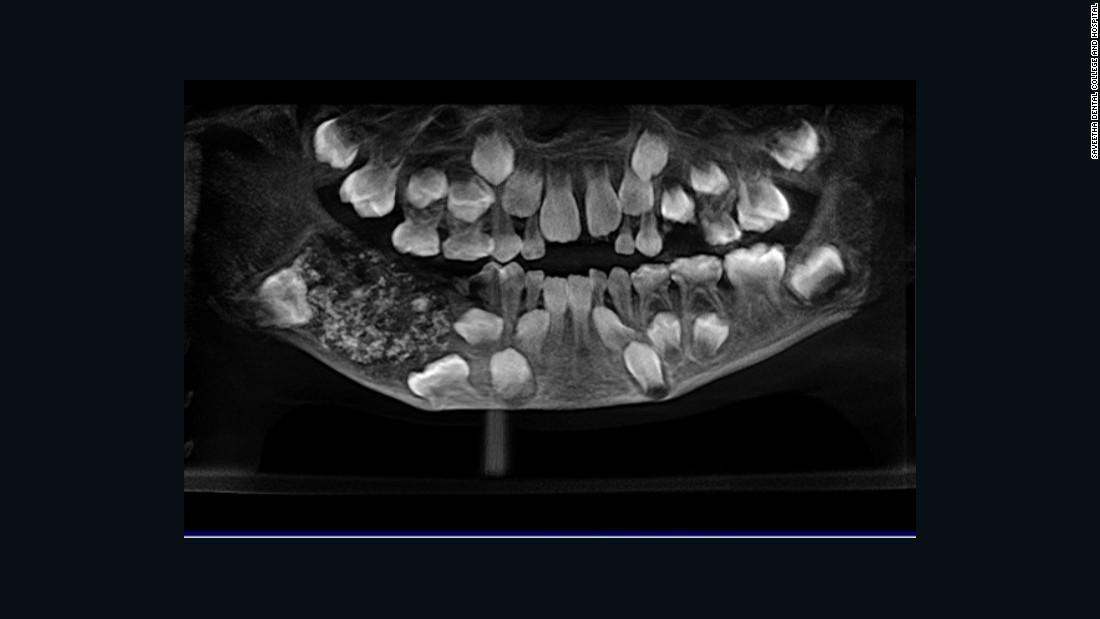

下あごの右側に、大量の「異常な歯」が詰まった嚢(のう)が見つかったという/Saveetha Dental College and Hospital

同病院の医師がCNNに語ったところによると、男の子のX線検査などを行って診察した結果、「異常な歯」が大量に入った嚢(のう)が見つかった。

子供の顎のレントゲンって異常な所以外はこんな感じ。

はじめて5歳の息子のレントゲン見た時に怖っ!って思ったわ。

あんなんでキレイに生え揃う永久歯すごい。

左側のモヤモヤした塊がその囊でしょ